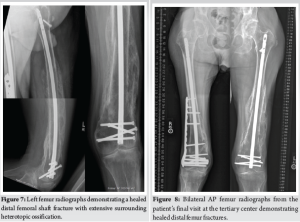

During the patient’s next follow-up visit, 1 month later, the patient complained of palpable hardware around his right knee. Repeat radiographs revealed a hypertrophic non-union with proximal migration of the nail and loosening of the distal interlocking screws (Fig. 5). He was initially treated conservatively; however, symptoms persisted for over 2 months. He then underwent removal of the right distal interlocking screws, augmentation with plate and screw fixation, and revision of the proximal interlocking screws. In a subsequent follow-up 3 weeks later, the patient noted a palpable mass around his left distal thigh. In addition, he developed a sacral decubitus ulcer that required referral to outpatient wound care. Conservative treatment with repeat imaging in 2 months was planned; however, the patient was lost to follow-up. The patient presented to the clinic 1 year later with complaints of palpable distal thigh masses bilaterally and feelings of heaviness in his legs. Radiographs revealed bilateral fracture healing with heterotopic ossification on the left, a well-fixed distal femur plate on the right, and no hardware failure (Fig. 6 and 7). The prominent left-sided heterotopic ossification and palpable right-sided distal femur plate caused significant discomfort. These complications greatly decreased his quality of life and caused him extreme distress. He was referred to a tertiary center for a second opinion, where radiographs revealed bilaterally healed distal femur fractures (Fig. 8 and 9). Removal of the right distal femur plate, left intramedullary nail, and left TTC nail was recommended to improve his quality of life. Unfortunately, the patient passed away from causes indirectly related to his orthopedic injuries before any further follow-up or surgical interventions could take place.